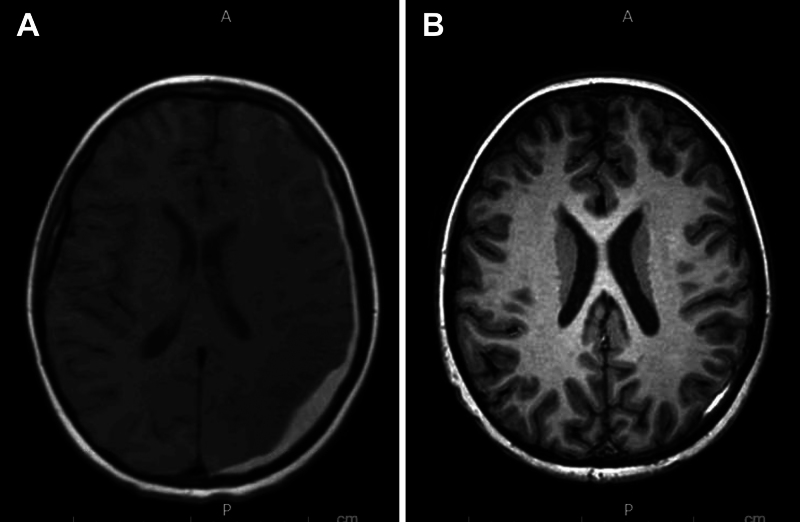

Observations: An 11-year-old male with newly diagnosed acute myeloid leukemia developed persistent, postural headaches following a lumbar puncture performed for diagnostic and therapeutic purposes. Initial imaging revealed a moderate left-sided SDH with midline shift, yet MRI of the lumbar spine failed to demonstrate an obvious CSF leak. Conservative management did not alleviate symptoms. Given the clinical picture of low CSF pressure, an EBP was administered, resulting in immediate headache improvement and subsequent radiographic evidence of SDH resolution.